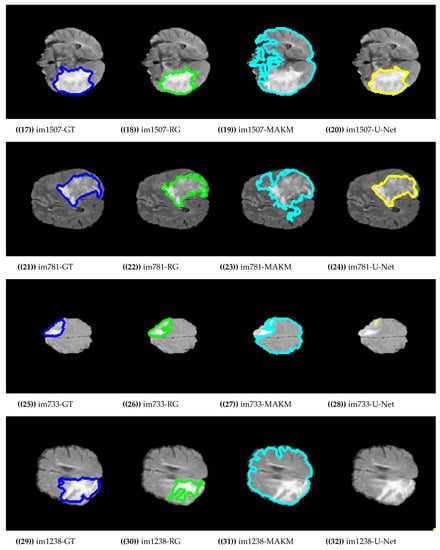

Figure 4 presented the segmentation results of the proposed algorithm, MAKM, and U-Net in terms of ROIs and their respective ground truths. For im274, im473, im551, im1507, im781, and im733 the proposed approach achieved ROIs which were almost the same as their respective ground truths (GTs). The proposed approach resulted in under-segmentation for im792 and im1238 as indicated in Figure 4. For the case of U-Net, the good segmentation results were observed only for im274, im551, im1507, and im781 and unable to detect the tumor region for im473, im792, im733, and im1238. In the case of MAKAM, over-segmentation results were achieved in almost all randomly selected brain images except for im274 where it detected the normal brain image part as abnormal.

Figure 4.

Segmentation results on BRATS2015 dataset.